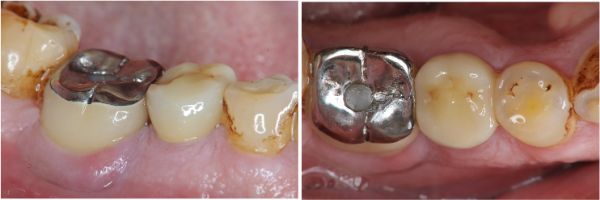

一體成型二氧化鋯全瓷冠

治療後口內照,患者的咀嚼機能逐漸恢復正常